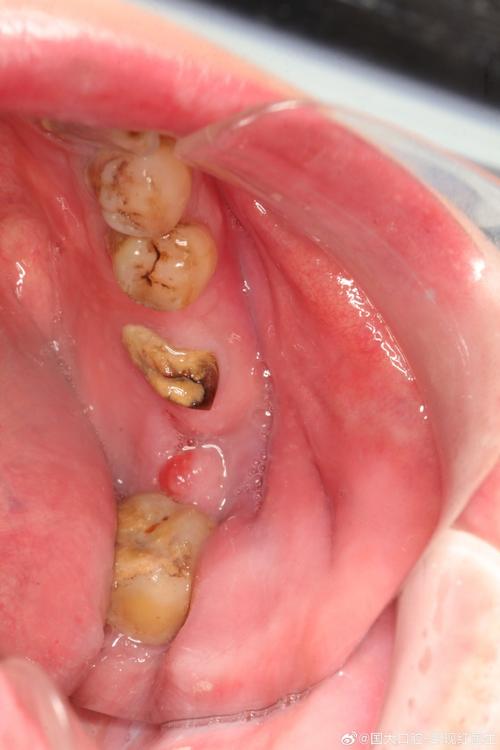

- 邻牙倾斜/移位: 两年时间,邻牙(旁边的牙齿)可能会向缺牙间隙倾斜,对颌牙(上下的牙齿)可能会伸长,这会改变原有的咬合关系和空间,可能需要:

- 邻牙/对颌牙的健康: 需要检查邻牙和对颌牙是否有龋坏、牙周病、需要根管治疗等问题,这些问题需要在种植手术前或同期处理,否则会影响种植牙的长期成功和咬合稳定。